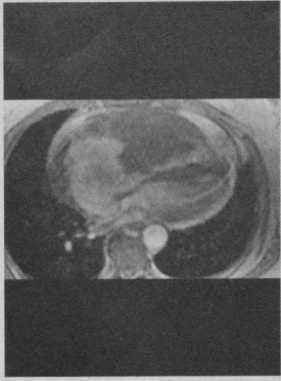

Обследование было направленно на выявление первичного опухолевого очага и распространенности онкологического процесса. При поступлении специфические жалобы (кардиалгии, ощущение аритмии, головокружения, одышка, неустойчивость АД) отсутствовали. Гемодинамика была стабильная. В связи с подозрением на вторичный характер изменений L4 была выполнена остеосцинтиграфия с 99mTc-пирфотехом, подтвердившая высокую вероятность вторичного опухолевого поражения костей скелета (рис. 1). Вечером 27.11.2016 г. произошло резкое ухудшение состояние в виде быстрого нарастания явлений острой сердечной (левожелудочковой) и дыхательной недостаточности. Пациент был переведён на вспомогательную вентиляцию лёгких и инотропную поддержку сердечной деятельности. По данным выполненных по cito трансторакальной эхокардиографии (рис. 2) и КТ-ангиографии (рис. 3) органов грудной клетки было выявлено объёмное образование левого предсердия, практически полностью заполняющее собой его полость и обтурирующее левое атриовентрикулярное отверстие. По неотложным показаниям в первой клинике хирургии (усовершенствования врачей) ВМедА в условиях искусственного кровообращения было выполнено удаление новообразования левого предсердия (рис. 4). В послеоперационном периоде явления острой сердечной и дыхательной недостаточности регрессировали. При гистологическом исследовании удалённого новообразования левого предсердия были выявлены признаки злокачественной мезенхимальной опухоли. Иммуногистохимическое исследование фрагмента опухоли позволило установить окончательный диагноз - «Недифференцированная плеоморфная саркома левого предсердия с прорастанием в межпредсердную перегородку и правое предсердие. Метастатическое поражение костей скелета: Th12-S2 позвонков, левой подвздошной кости, правой плечевой, лобковой, бедренной, большеберцовой костей».

Рис. 1. Результаты остеосцинтиграфии скелета с 99mTc-пирфотехом. Были выявлены зоны повышенного накопления препарата в проекции правого плечевого сустава (свыше 90%), в проекции лобковой кости слева (свыше 65%), в проекции нижней трети диафиза левой бедренной кости (свыше 35%), в проекции нижней трети правой голени (свыше до 97%). Зоны повышенного накопления препарата указаны стрелкой. Рис. 2. Трансторакальная эхокардиография (четырёхкамерная верхушечная позиция). В левом предсердии определяется объёмное образование, занимающее почти всю его полость (A, B) и пролабирующее в левый желудочек в диастолу с обструкцией атриовентрикулярного отверстия (C, D). Рис. 3. КТ-ангиография органов грудной клетки (фронтальная проекция).